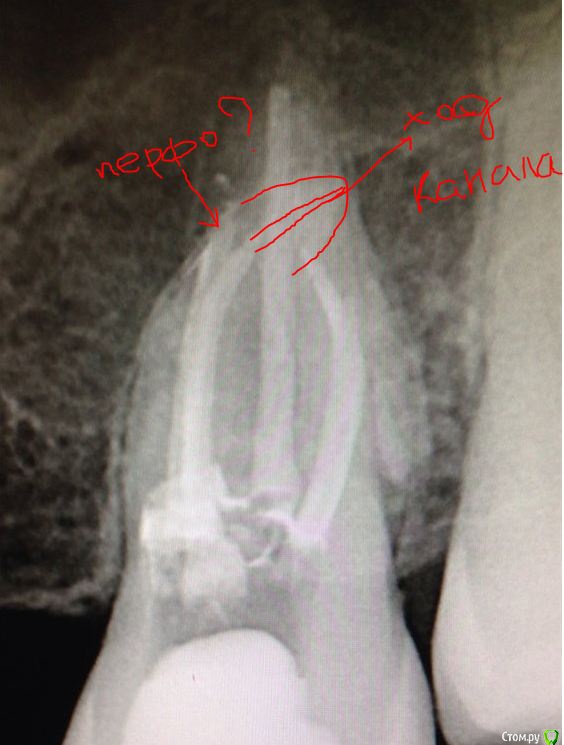

SSTi Опубликовано 9 мая, 2015 Автор Поделиться Опубликовано 9 мая, 2015 ищем клад) кто нашел косяк?http://s008.radikal.ru/i303/1505/00/12db93a3e1ef.jpg Ссылка на комментарий

Паращук Роман Опубликовано 9 мая, 2015 Поделиться Опубликовано 9 мая, 2015 апикальное перфо Ссылка на комментарий

SSTi Опубликовано 9 мая, 2015 Автор Поделиться Опубликовано 9 мая, 2015 нет. это мб и мб2 Кажется так.. Ссылка на комментарий

SSTi Опубликовано 9 мая, 2015 Автор Поделиться Опубликовано 9 мая, 2015 это меньшее из зол. здесь есть еще "3 в одном")апикальное перфо Ссылка на комментарий

Kolchanov Опубликовано 10 мая, 2015 Поделиться Опубликовано 10 мая, 2015 Там в устье МВ что-ли перфа еще?Вот до чего эти поиски доводят. Либо потом пропадают и отламывают стенку подрытую. Надо билдапить сразу прям. Будет вот, как здесь и привет. Ссылка на комментарий

SSTi Опубликовано 10 мая, 2015 Автор Поделиться Опубликовано 10 мая, 2015 перфо нет Там в устье МВ что-ли перфа еще?Вот до чего эти поиски доводят. Либо потом пропадают и отламывают стенку подрытую. Надо билдапить сразу прям. Будет вот, как здесь и привет.смотрите в дб Ссылка на комментарий

Л Ю С Я Опубликовано 10 мая, 2015 Поделиться Опубликовано 10 мая, 2015 (изменено) Ступень или транспортация канала ? Изменено 10 мая, 2015 пользователем Л Ю С Я Ссылка на комментарий

_omega- Опубликовано 10 мая, 2015 Поделиться Опубликовано 10 мая, 2015 (изменено) перфо нет смотрите в дбМожет еще 1канал в дб? Там очертания есть?! И ступенька по моему Изменено 10 мая, 2015 пользователем _omega- Ссылка на комментарий

SSTi Опубликовано 10 мая, 2015 Автор Поделиться Опубликовано 10 мая, 2015 http://s56.radikal.ru/i151/1505/59/5a53efc9e1e1.jpg http://s019.radikal.ru/i639/1505/9c/8e6d63304701.jpg в первое посещение был сломан профайл 20,04 в дб ( каналы были оооооочень узкие ), на кой черт я его взял в руки.оставлена гидроокись. во второе - обломок обошел 10, и сломал рядом 15 начал обходить 2 обломка. обошел) начал расширяться и ломанул 25. итого - 3 обломка в дб. вот такой я криворук) если честно - меня в конце уже бесил этот зуб и я сам Ссылка на комментарий